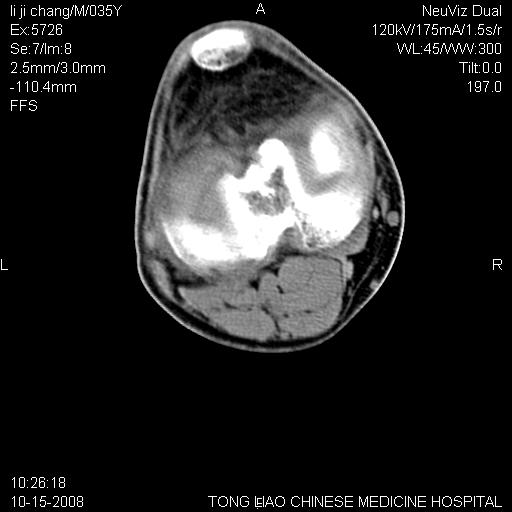

男,35岁,骨科诊断骨性关节炎。继往使用过激素,现股骨头坏死。膝关节病变,请会诊

一元论-----亦考虑为坏死

支持考虑无菌坏死

支持无菌坏死伴退行性骨关节病.

剥脱性骨软骨炎:是一种关节下软骨及软骨下骨缺血性坏死。

35岁就退变得这么利害???不太可能吧?zsl6918老兄??是否要考虑一下骨关节结核呀。

支持 无菌性坏死伴退行性骨关节病。